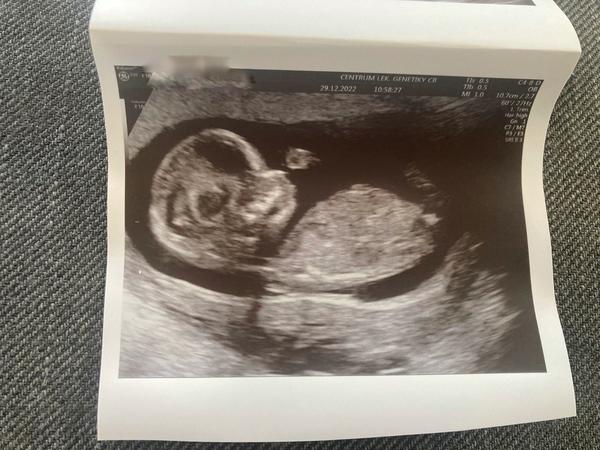

Ahoj🙂 13+6 poznal by někdo pohlaví? Dekuju

@tynyee řekla bych že je to holčička 😊❤️